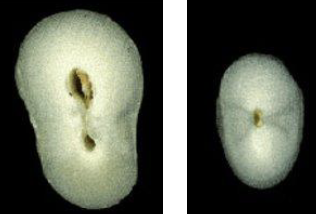

What is the anatomical variation in this lateral incisor?

Talon cusp